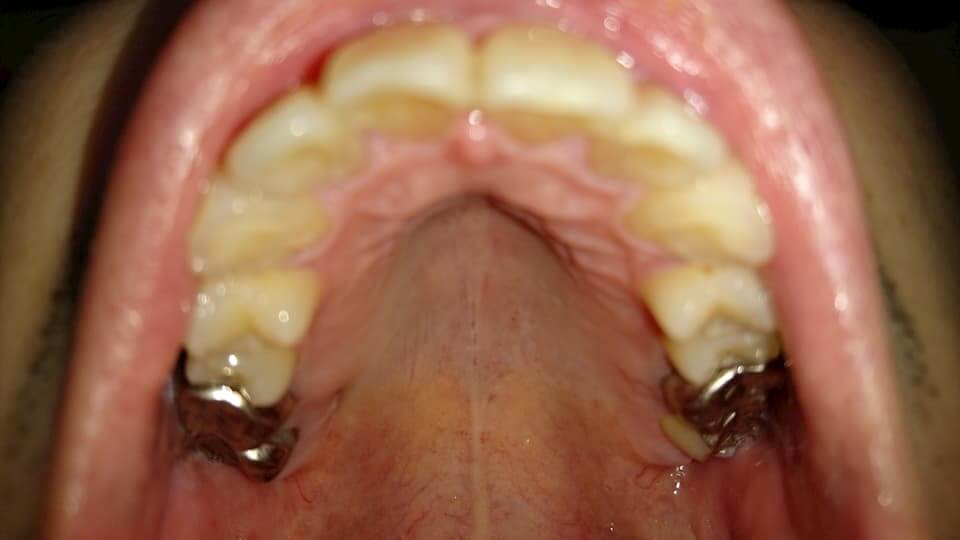

歯の写真